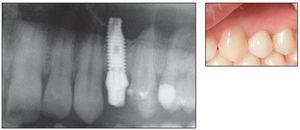

Figuras 4d y 4e Radiografía de seguimiento al año y visión clínica del implante con su corona provisional.

Acto seguido, se colocaron los implantes de acuerdo con un procedimiento de un estadio (figura 4c). Se permitieron diferentes procedimientos de cicatrización: en seis implantes la carga fue inmediata, en 24 la carga fue precoz entre una semana y 3 meses y en 10, la carga se produjo a los 3-6 meses debido a demoras del paciente.

En el momento de la cicatrización, se examinó la movilidad del implante y se tomaron las medidas clásicas para la rehabilitación protésica.

Se procedió a un seguimiento de los implantes al término del correspondiente período de cicatrización a los 3, 6 y 12 meses después de la carga (figuras 4d y 4e) y, por lo tanto, para los objetivos de este estudio. Los criterios de éxito incluyeron: 1) extracción sin fractura del diente/raíz; 2) colocación eficaz y estabilidad primaria del implante; 3) estabilidad del implante en cada visita de seguimiento; 4) ausencia de dolor o de cualquier sensación subjetiva; 5) ausencia de infección recurrente periimplante y 6) ausencia de radiotransparencia continua alrededor del implante.